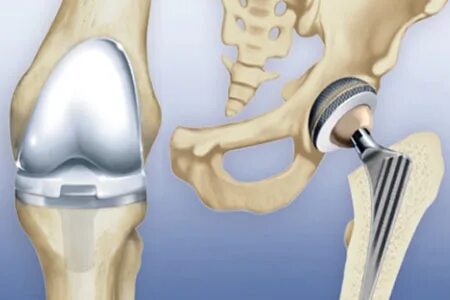

Эндопротезирование коленного сустава чебоксары